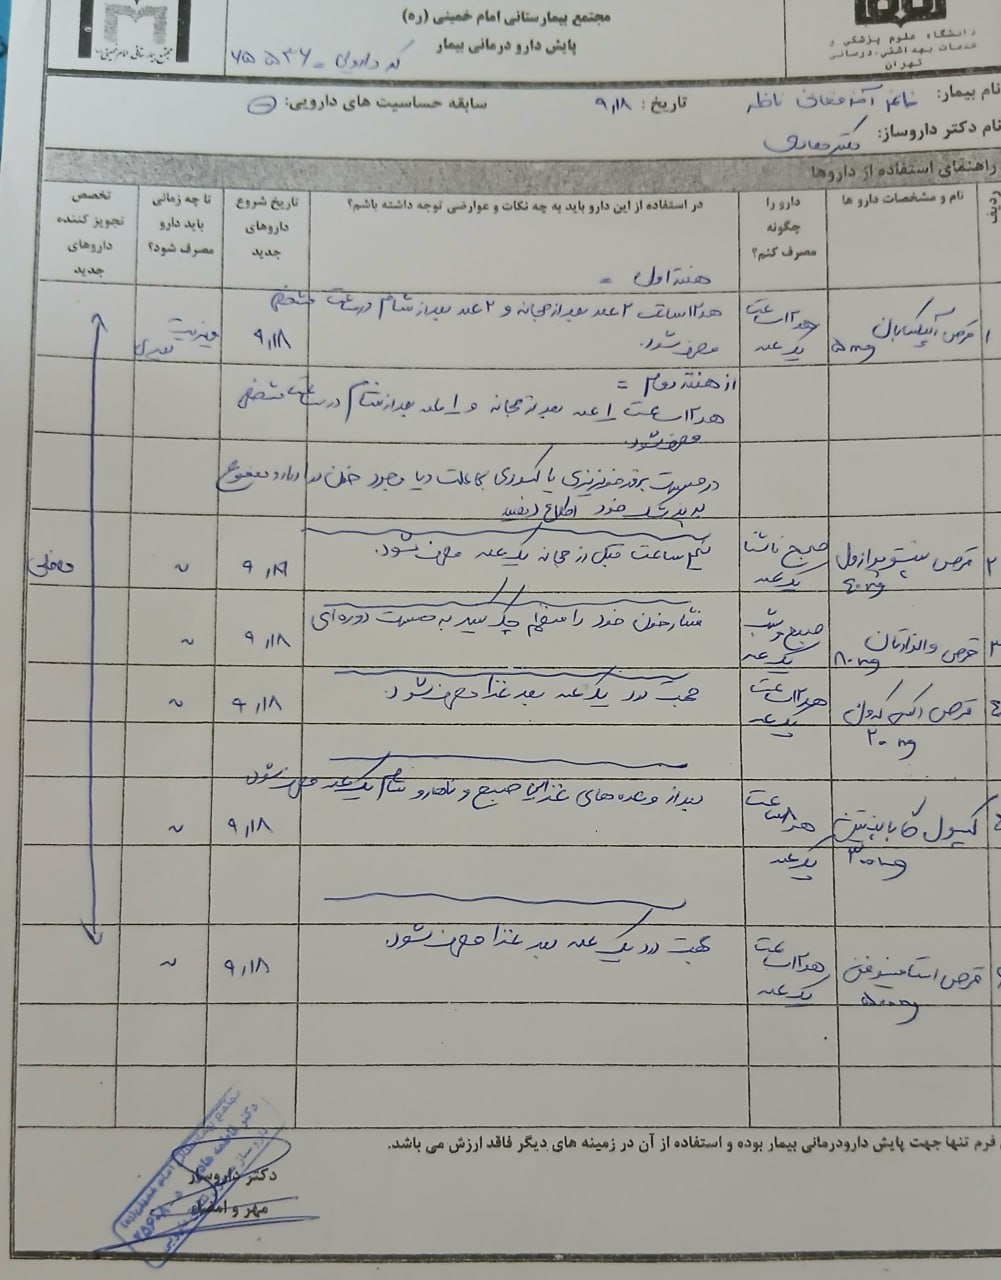

Pentomid 40

Valsartan 80

Apixaban 5

Caltonix 200 I.U.

gabapentin 300

(تصویر مربوط به این مراجعه نیست) Other:

(تصویر مربوط به این مراجعه نیست) Other:

(تصویر مربوط به این مراجعه نیست) Other:

(تصویر مربوط به این مراجعه نیست) Other:

(تصویر مربوط به این مراجعه نیست) Other:

(تصویر مربوط به این مراجعه نیست) Other:

(تصویر مربوط به این مراجعه نیست) Other:

(تصویر مربوط به این مراجعه نیست) Other:

(تصویر مربوط به این مراجعه نیست) Other:

(تصویر مربوط به این مراجعه نیست) Other:

(تصویر مربوط به این مراجعه نیست) Other:

(تصویر مربوط به این مراجعه نیست) Other:

(تصویر مربوط به این مراجعه نیست) Other:

(تصویر مربوط به این مراجعه نیست) Other:

(تصویر مربوط به این مراجعه نیست) Other:

(تصویر مربوط به این مراجعه نیست) Other:

(تصویر مربوط به این مراجعه نیست) Other:

(تصویر مربوط به این مراجعه نیست) Other:

(تصویر مربوط به این مراجعه نیست) Other:

(تصویر مربوط به این مراجعه نیست) Other:

(تصویر مربوط به این مراجعه نیست) Other:

(تصویر مربوط به این مراجعه نیست) Other:

(تصویر مربوط به این مراجعه نیست) Other:

(تصویر مربوط به این مراجعه نیست) Other:

(تصویر مربوط به این مراجعه نیست) Other:

(تصویر مربوط به این مراجعه نیست) Other:

(تصویر مربوط به این مراجعه نیست) Other:

(تصویر مربوط به این مراجعه نیست) Other:

(تصویر مربوط به این مراجعه نیست) Other:

(تصویر مربوط به این مراجعه نیست) Other:

(تصویر مربوط به این مراجعه نیست) Other:

(تصویر مربوط به این مراجعه نیست) Other:

(تصویر مربوط به این مراجعه نیست) Other:

(تصویر مربوط به این مراجعه نیست) Other:

(تصویر مربوط به این مراجعه نیست) Other:

(تصویر مربوط به این مراجعه نیست) Other:

(تصویر مربوط به این مراجعه نیست) Other:

(تصویر مربوط به این مراجعه نیست) Other:

(تصویر مربوط به این مراجعه نیست) Other:

(تصویر مربوط به این مراجعه نیست) Other:

(تصویر مربوط به این مراجعه نیست) Other:

(تصویر مربوط به این مراجعه نیست) Other:

(تصویر مربوط به این مراجعه نیست) Other:

(تصویر مربوط به این مراجعه نیست) Other:

(تصویر مربوط به این مراجعه نیست) Other:

(تصویر مربوط به این مراجعه نیست) Other:

(تصویر مربوط به این مراجعه نیست) Other: